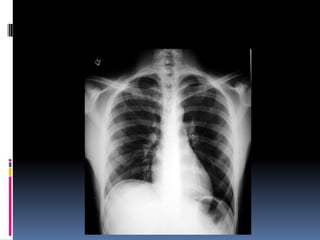

Positioning / Rotation

Does the thoracic spine align in the center of the

sternum and between the clavicles?

Clavicles – equidistant from spine

Determine side – ? L/R

 Gastric bubble should be on the left ( normally )

Positioning / Rotation Doesthe thoracic spine align in the center of the sternum and between the clavicles? Clavicles – equidistant from spine

Determine side –? L/R  Gastric bubble should be on the left ( normally )